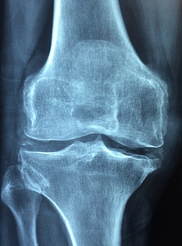

2. 관절 부종: 류마티스 관절염은 활막이라는 조직에 염증이 생기면서 관절 주위에 물이 차고 붓게 됩니다. 이로 인해 손가락이나 발가락의 마디가 부풀어 보이거나, 신발이나 반지가 잘 맞지 않는 경우가 있습니다.

3. 관절 통증: 류마티스 관절염은 주로 좌우 대칭적으로 작은 관절부터 통증이 시작됩니다. 통증은 압박감이나 쑤시는 느낌으로 나타나며, 활동을 하면 줄어들고, 쉬면 더 심해지는 경향이 있습니다.

4. 관절 열감: 염증 반응으로 인해 관절 부위가 따뜻하고 붉어지는 증상입니다. 통증이 있는 관절을 만지면 열을 느낄 수 있으며, 가끔 발열도 동반될 수 있습니다.